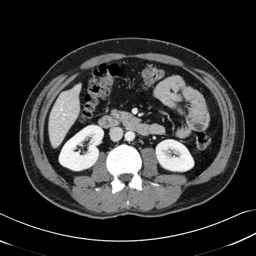

In many clinical settings, the use of both Computed Tomography (CT) and Magnetic Resonance (MRI) is necessary to pursue a thorough understanding of the patient's anatomy and to plan a suitable therapeutical strategy; this is often the case in MRI-based radiotherapy, where CT is always necessary to prepare the dose delivery, as it provides the essential information about the radiation absorption properties of the tissues. Sometimes, MRI is preferred to contour the target volumes. However, this approach is often not the most efficient, as it is more expensive, time-consuming and, most importantly, stressful for the patients. To overcome this issue, in this work, we analyse the capabilities of different configurations of Deep Learning models to generate synthetic CT scans from MRI, leveraging the power of Generative Adversarial Networks (GANs) and, in particular, the CycleGAN architecture, capable of working in an unsupervised manner and without paired images, which were not available. Several CycleGAN models were trained unsupervised to generate CT scans from different MRI modalities with and without contrast agents. To overcome the problem of not having a ground truth, distribution-based metrics were used to assess the model's performance quantitatively, together with a qualitative evaluation where physicians were asked to differentiate between real and synthetic images to understand how realistic the generated images were. The results show how, depending on the input modalities, the models can have very different performances; however, models with the best quantitative results, according to the distribution-based metrics used, can generate very difficult images to distinguish from the real ones, even for physicians, demonstrating the approach's potential.